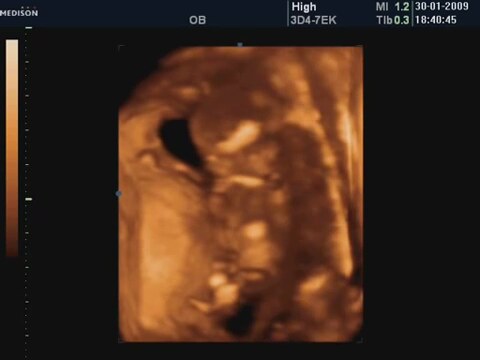

14 Haftalik Bebeğin 4 Boyutlu Ultrason Görüntüsü